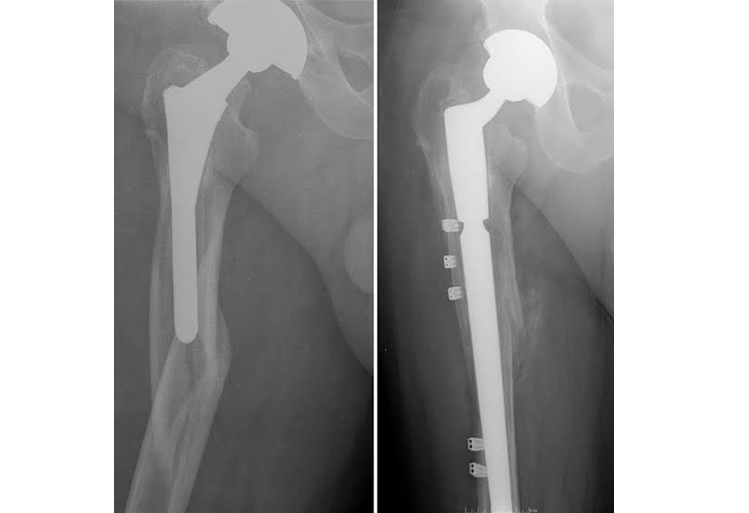

A revision hip replacement surgery is a surgical procedure to replace a worn out or failed hip replacement implant. Hip replacements are among the most common procedures performed by orthopedic surgeons. This surgery is generally very successful and has excellent results in the vast majority of patients.